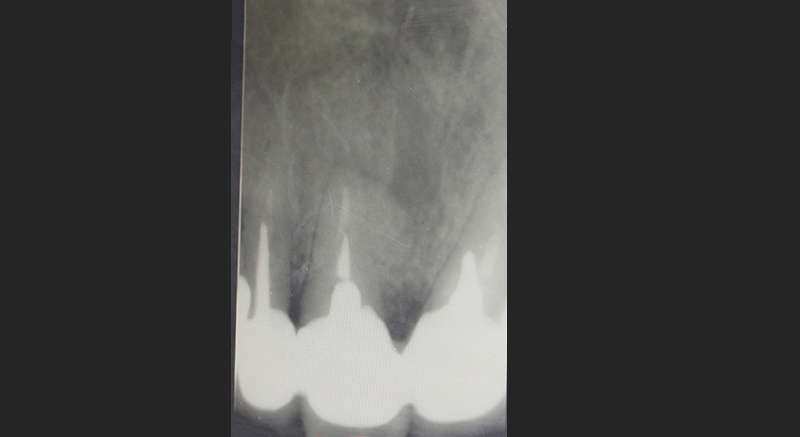

В медиальной области 11-го зуба пациентки была резорбция кости. Для лечения была проведена пародонтальная операция:

1.сглаживание поверхности корня;

2.добавление костной ткани;

3.установка мембраны.